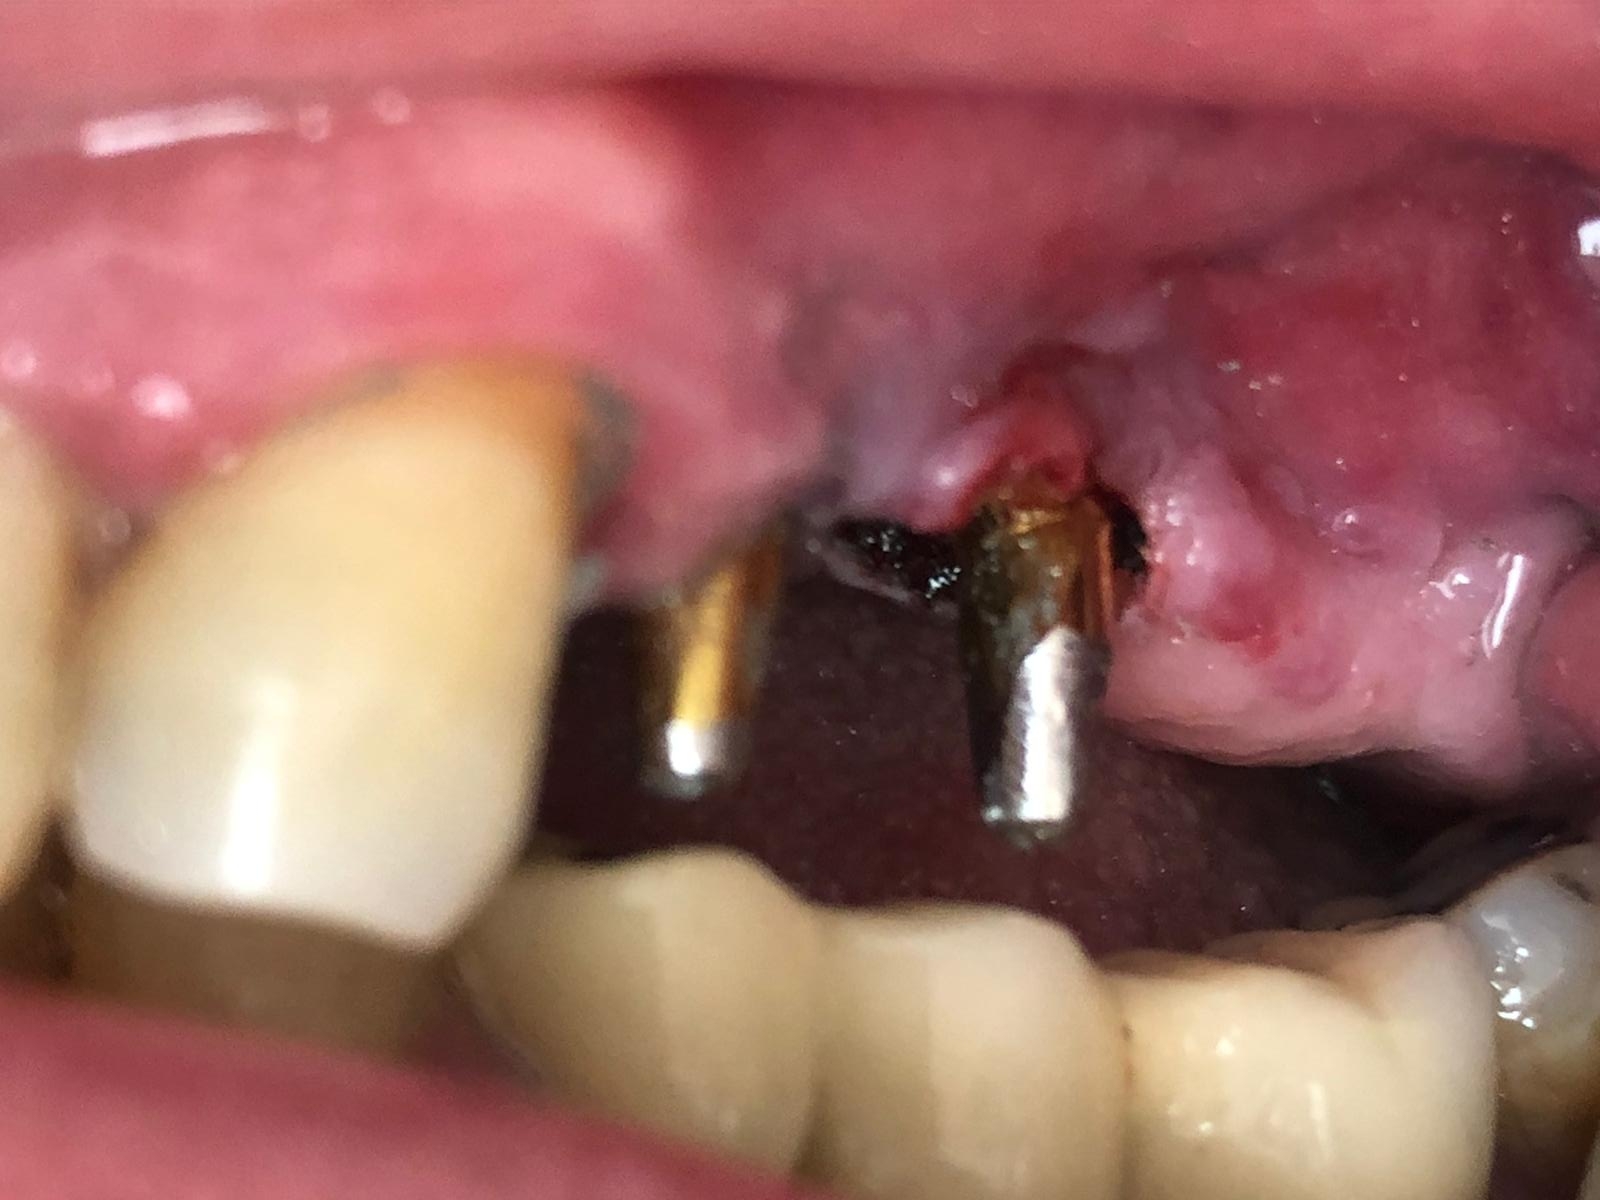

El paciente es un gran bruxómano y rompió hace tres años el implante Mesial (flecha en la imagen), pero no rompió solo la rosca del aditamento, sino también la cabeza del implante entera, quedando solo un resto de hueco roscado (comparar la anatomía de los implantes) en el que lo único que se pudo hacer, debido a que el implante tenía la conexión rota, fue roscar el aditamento ASATIM, pero solo la zona roscada y no el refuerzo y cono del implante, el cual había desaparecido (flecha en la imagen).

En nuestra clínica pusimos un aditamento de tornillo pasante en el implante distal. Y con esto se rehízo la prótesis. Así ha estado hasta este momento en el que aparece con la rosca de este tornillo pasante distal roto y dentro del implante (círculo en la imagen).